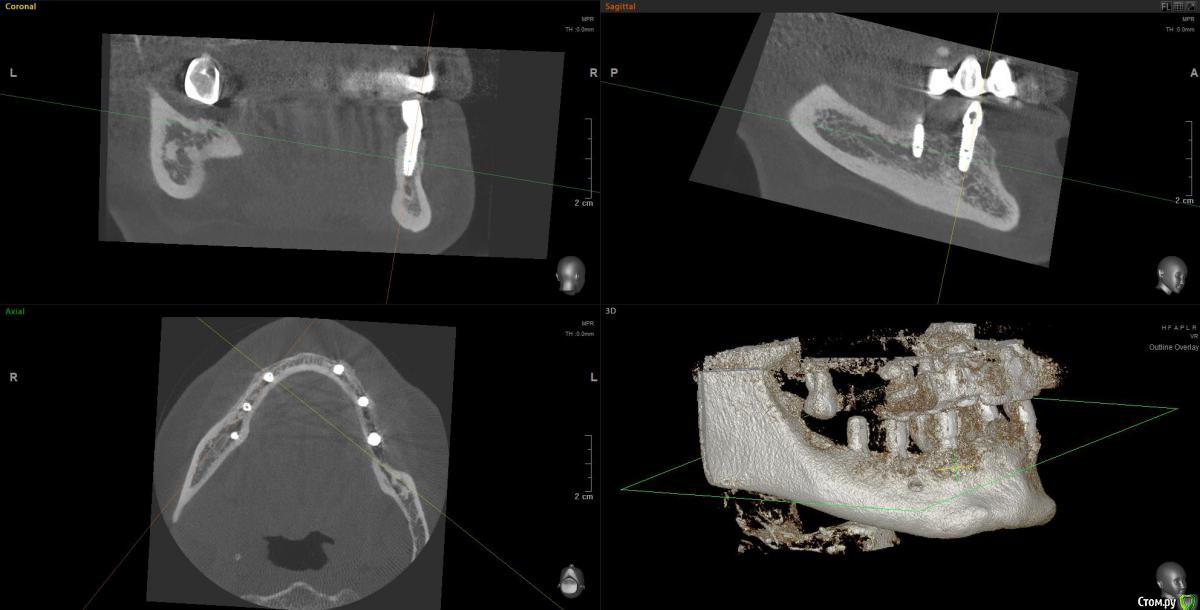

Kostoprav Опубликовано 14 июня, 2019 Поделиться Опубликовано 14 июня, 2019 Ксено+ауто +i prf, поверх титановых мембран перикард. кт через 5 мес.при и создании прикрепленки использовалась свиная дерма отечественного производителя 4 Ссылка на комментарий